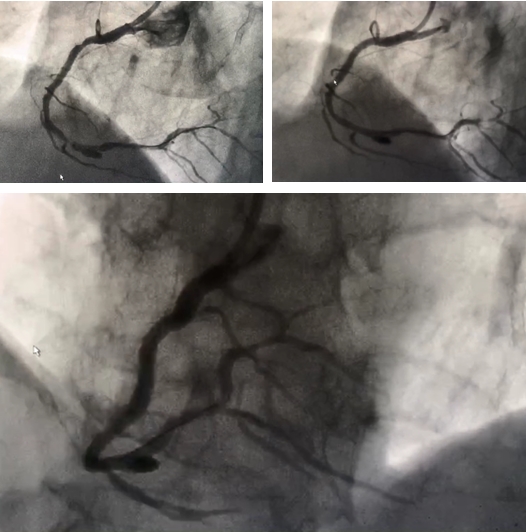

此次实施冠状动脉瘤介入封堵术的病人为一70岁老年男性,因“头昏2月,加重伴胸闷1周”到老年病科就诊,患者11年前曾因冠心病在我院实施冠状动脉介入手术,于右冠状动脉近端及远端植入支架治疗,入院后于2018年5月24日行冠状动脉造影检查发现患者原右冠状动脉近端及远端支架内无异常,中远端可见重度狭窄,狭窄后可见直径约7mm动脉瘤,由于瘤体较大,存在随时破裂导致患者出现猝死的风险,因此必须进行处理,目前常用的技术中普通心脏支架无法封住较大瘤体,而在瘤体部位植入带膜支架虽可以封住瘤体,但是带膜支架再狭窄发生率高,不利于患者预后,经过慎重考虑并与患者沟通交流同意后,李兴升主任决定联合多学科择期为患者实施冠状动脉瘤体介入封堵术。经过细致的准备,2018年5月28日,李兴升主任在神经外科陈维福教授和放射科杨伟技师的协助下,为患者成功实施了冠状动脉瘤介入封堵术,李主任首先处理了患者右冠状动脉狭窄,通过球囊扩张后植入支架,然后在陈维福教授帮助下成功将弹簧圈释放进入冠状动脉瘤体内,造影显示右冠状动脉远端狭窄解除,冠状动脉瘤体成功封堵,介入室响起了热烈的掌声,这掌声不仅是对我科成功完成重庆地区首例冠状动脉瘤介入封堵术的鼓励,更是对神经外科及放射科支持的感激,还饱含着对手术成功后患者转为为安的喜悦之情!